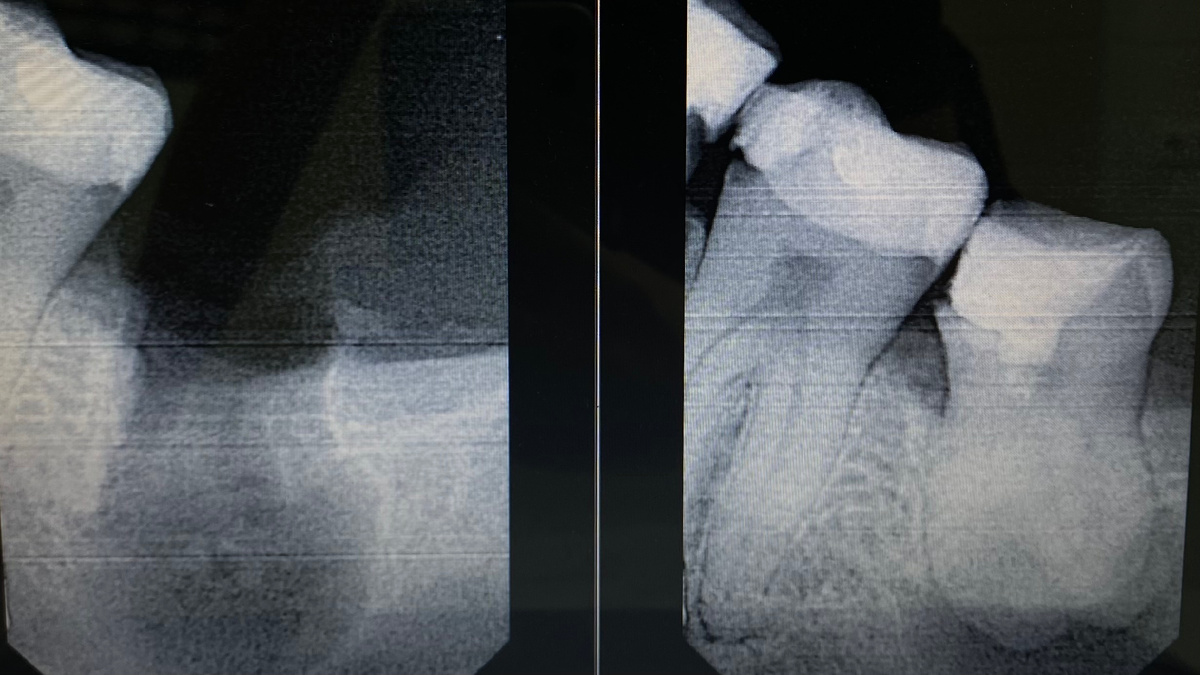

Удаленный зуб «мудрости»